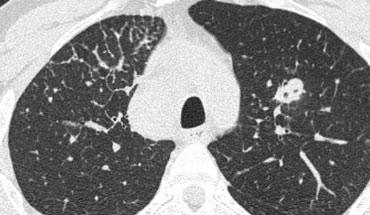

Ca lâm sàng minh họa: Ung thư lan tràn theo đường bạch huyết

Hình ảnh

Dày vách khu trú, không đều ở thùy trên phổi phải trên bệnh nhân có tiền sử ác tính đã biết. Dấu hiệu này điển hình cho ung thư phổi lan tràn theo đường bạch huyết.

Các đặc điểm hỗ trợ chẩn đoán bao gồm:

- Hạch bạch huyết trung thất

- Tổn thương dạng nốt ở phổi trái, nhiều khả năng là di căn.

Ung thư phổi lan tràn theo đường bạch huyết (PLC):

- Trong 50% trường hợp, dày vách có tính chất khu trú hoặc một bên, giúp phân biệt với các nguyên nhân khác (ví dụ: sarcoidosis, phù phổi do tim).

- Hạch bạch huyết rốn phổi có thể thấy trong 50% bệnh nhân, và thường có tiền sử bệnh ác tính.